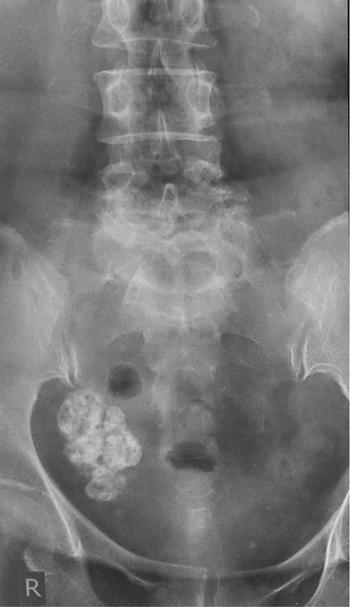

Venkatraman Indiran Bridging vessel sign Multiple vascular channels (white arrows) connecting uterus (black arrow) to an adjacent pelvic mass on imaging studies, is known as the ‘bridging vessel’ or ‘bridging vascular’ sign. Originally described on colour Doppler imaging, but also seen on computed tomography (CT) or magnetic resonance imaging (MRI). Helps in differentiating a mass of uterine origin, typically a subserosal fibroid, from other pelvic masses. Sensitivity and specificity of ‘bridging vessel sign’ in identifying subserosal fibroids range from 90% to 100%. (Best seen when subserosal fibroid is larger than 3 cm in diameter.) Ovarian masses invading the uterus may rarely produce a falsely positive bridging vessel sign. Broccoli sign Submucosal uterine leiomyoma prolapsing into the endocervical canal, along with its stalk in the uterine cavity on sagittal T2-weighted images together is called as ‘broccoli sign’ (white arrow). Submucosal uterine leiomyoma Bunch of grapes Intrauterine mass with cystic spaces without any associated foetal parts on ultrasound (white arrows) classically gives a ‘snow storm’ or ‘bunch of grapes’ appearance. Complete hydatidiform mole Hourglass sign Deep infiltrating endometriosis (DIE) affecting the posterior urinary bladder wall, usually in the midline, causes loss of its distensibility, resulting an hourglass configuration of urinary bladder. Deep infiltrating endometriosis (DIE) Hyperechoic line sign Normal endometrium surrounding the endometrial polyp on ultrasound appear as a hyperechoic rim on transvaginal ultrasound is called as ‘hyperechoic line sign’. Hyperechoic line sign represents a focal intracavitary lesion. Endometrial polyp Indian head dress sign/moose antler sign In deep infiltrating endometriosis (DIE), adhesions between the anterior wall of rectosigmoid and posterior wall of uterus, stretches the muscular layer of the bowel and creates an infiltrative nodule with parallel lines that extend from the adhesion to the rectosigmoid. This is called as ‘Indian head dress sign/moose antler sign’ (white arrow). This is seen on sagittal T2-weighted images as well as transvaginal ultrasound. Deep infiltrating endometriosis (DIE) Interstitial line sign An echogenic line that extends into the upper regions of the uterine horn and borders the margin of the intramural gestational sac is called as the ‘interstitial line sign’ (white arrow). Seen best on transabdominal/transvaginal ultrasound. Specific finding of interstitial pregnancy Mushroom cap sign Mushroom-shaped lesion which is seen displaced into the bowel lumen in patients with solid invasive endometriosis of the rectosigmoid colon on axial or sagittal T2-weighted MRI is called as ‘mushroom cap sign’ (red box and white arrow). Low signal intensity base of the mushroom corresponds to hypertrophy and fibrosis of the muscularis propria, whereas the high intensity cap represents oedematous mucosa and submucosa. Deep infiltrating endometriosis (DIE) Pedicle artery sign Feeding vessel sign Central vessel entering the endometrium from the surrounding myometrium colour Doppler imaging of the endometrium in endometrial polyps is called as pedicle artery sign (white arrow). Endometrial polyps in women with postmenopausal bleeding. (Sensitivity of 76.5%; specificity of 95.3%.) Popcorn ball calcification Dense, amorphous calcifications of uterine fibroids seen on the plain radiographs is called as ‘popcorn calcification’ (white arrow). Confluent, coarse calcification constitutes the most specific radiographic sign of a benign uterine fibroid; but only 10% or fewer of fibroids show calcification. Question mark sign of uterus The uterine corpus that is flexed backward with the fundus of the uterus facing the posterior pelvic compartment and the cervix directed anteriorly toward the urinary bladder, is called as question mark sign of uterus (white arrow). Also called as comma-shaped uterus. 93% specificity and 75% sensitivity in diagnosing adenomyosis uterus. Sliding organs’ sign When the uterus and ovaries glide freely over the posterior and anterior organs (such as rectum and urinary bladder, respectively) during real-time dynamic transvaginal sonography, it is called as ‘positive sliding organs’ sign’. In case of adhesions due to endometriosis, free gliding of organs is absent and is called as negative sliding sign. Snowstorm sign Grainy appearance with low-level homogeneous internal echoes which move slowly downward due to their viscosity seen in endometrioma on transvaginal ultrasound is called as snowstorm sign. Endometriomas Split fibre sign Presence of curvilinear T2 hypointense strands within the degenerated leiomyoma separated by the fluid accumulation and oedema is called as the ‘split fibre’ sign. Split fibre sign on T2-weighted MRI can be used to differentiate hydropic degeneration from other conditions like malignant change. Three-line sign or triple line sign or trilaminar appearance Shortly before ovulation, two additional bright linear echoes outline two hypoechoic layers of endometrium with a central hyperechoic line in the endometrium (white arrow). It is called as the ‘three-line sign’ or ‘triple line sign’ or trilaminar appearance. A triple-line pattern with a moderate endometrial thickness is associated with a good clinical outcome on in-vitro fertilization. Venetian blind shadowing Also known as ‘rain shower’ appearance Heterogeneous myometrial appearance due to hyperechoic heterotopic endometrial tissue and hypoechoic hyperplastic smooth muscle appearing as vertical linear bands of shadows on ultrasound is called as ‘Venetian blind shadowing’. Classically described in uterine adenomyosis; sometimes in uterine fibroids also. Bead on strings sign Thickened endosalpingeal longitudinal folds within a dilated fallopian tube without wall thickening appears as small mural nodules on cross-sectional images on ultrasound is called as ‘bead on strings’ appearance. Seen in chronic salpingitis Beaded tube Multiple constrictions along the course of fallopian tube may form due to scarring is seen in genitourinary tuberculosis and shows a ‘beaded’ appearance. Female genital tuberculosis Cogwheel sign Thickened endosalpingeal longitudinal folds within a dilated fallopian tube with thickened wall appears as small mural nodules on cross-sectional images across the long axis of the fallopian tube on ultrasound (white arrows) produce a characteristic ‘cogwheel’ appearance. Seen in acute salpingitis. The presence of thickened longitudinal folds is pathognomonic for hydrosalpinx. Cobblestone tube Rounded filling defects in cases of fallopian tube tuberculosis are called as the cobblestone pattern. Is an effective radiographic sign of intraluminal scarring and adhesions. Female genital tuberculosis Golf club tube Occlusion of the isthmus or fimbrial end of the fallopian tube and filling up of the tube with serous or clear fluid produces a moderate dilatation at the fimbrial end, produces a ‘golf club–like appearance’. Female genital tuberculosis Halo sign Thin radiolucency seen separating the loculated peritubal collection from the dilated tube, is known as the ‘halo sign’. This radiolucent halo represents the thickened wall of the tube. Female genital tuberculosis Incomplete septation sign Thin linear structures appearing to protrude into the tubular cystic adnexal structures, but not touching the opposite walls is called ‘incomplete septation sign’ of hydrosalpinx. Apparent septae are due to apposition of the inner walls of the dilated and folded fallopian tube. Hydrosalpinx Pipe stem tube Rigid contour of the fallopian tube seen in cases of fallopian tube tuberculosis is called as ‘pipe stem appearance’. Female genital tuberculosis Leash sign Typical eccentric leash of vessels on colour Doppler (white arrow) showing a low resistance placental type of flow on spectral Doppler in fallopian tube ectopic pregnancies is called as leash sign.